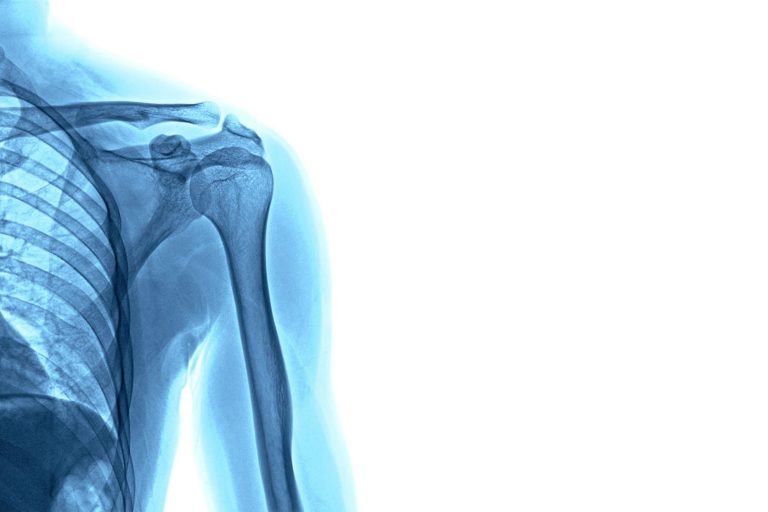

Die Magnetresonanztomographie (MRT) ist ein modernes, strahlungsfreies Bildgebungsverfahren, das vollständig ohne Röntgenstrahlen auskommt. Sie eignet sich in besonderem Maße zur detaillierten Darstellung von Weichteilstrukturen wie Gehirn und Rückenmark, Sehnen und Muskeln, Bandscheiben sowie inneren Organen wie Leber, Nieren, Bauchspeicheldrüse und Milz. Darüber hinaus lassen sich auch knöcherne Strukturen wie Wirbelkörper und Gelenke sowie deren Bestandteile…